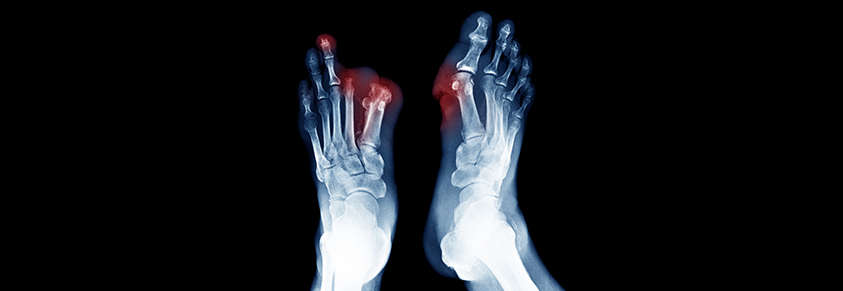

„Je eher Patienten mit Schmerzen im Bein oder Fuß, Verfärbungen der Haut oder offenen Wunden an den Beinen zum Gefäßspezialisten gehen, umso besser ist die Chance, dass ein Absterben der Gliedmaßen und somit eine Amputation verhindert werden kann“, so Lichtenberg.

Jedes Jahr müssen in Deutschland rund 60.000 Zehen, Füße oder sogar Beine amputiert werden. Bei rechtzeitiger Behandlung könnte dies verhindert werden!